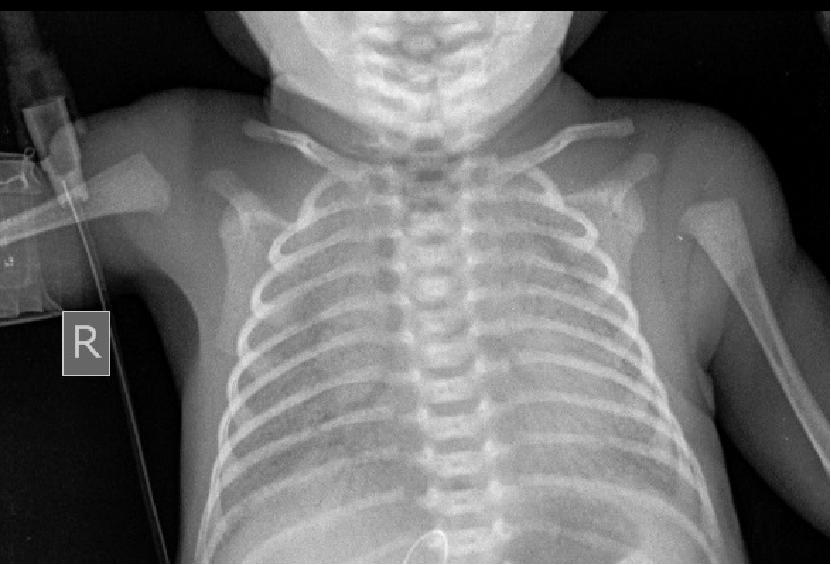

可有合并症:早产儿呼吸窘迫综合征机械通气1天后合并气胸

出生1天X线行机械通气